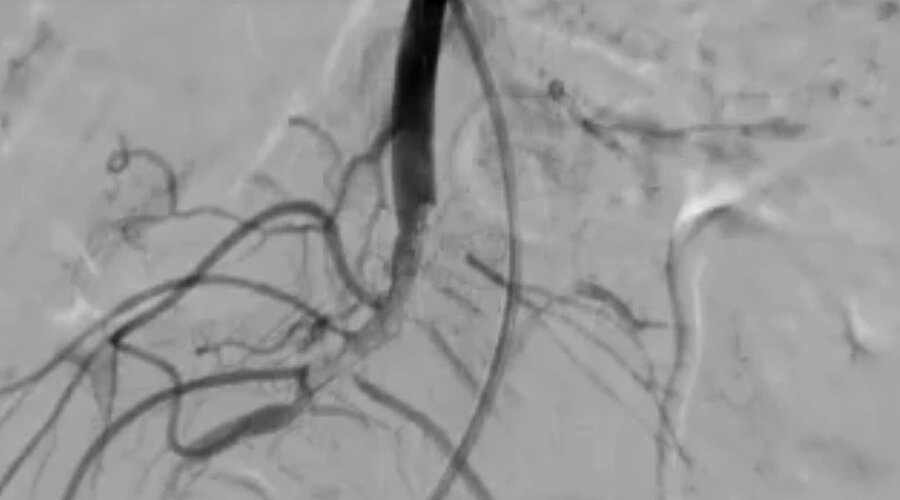

В Балаково медики провели уникальную операцию, использовав нестандартный способ лечения. Проявив сообразительность и мастерство, Балаковские врачи спасли пенсионерку с тяжелым диагнозом. Как сообщает Балаковская городская клиническая больница (БГКБ), в приемное отделение поступила 78-летняя пенсионерка с тромбозом кишечника. Отличить на ранних этапах данное заболевание от других очень сложно, и окончательный диагноз врачи поставили уже непосредственно перед операцией. Медикам пришлось не только удалить омертвевшую часть кишечника, но и удалось необычным способом восстановить кровообращение в сосудах. По информации БГКБ, пенсионерку после операции внимательно наблюдали в течение недели, и сейчас уже выписали из больницы. А подробности уникальной операции балаковских медиков смотрите в репортаже БГКБ. Фото, видео: БГКБ Читайте также: Балаковца обвинили в нарушении городского дизайн-кода

Как сообщает Балаковская городская клиническая больница (БГКБ), в приемное отделение поступила 78-летняя пенсионерка с тромбозом кишечника. Отличить на ранних этапах данное заболевание от других очень сложно, и окончательный диагноз врачи поставили уже непосредственно перед операцией. Медикам пришлось не только удалить омертвевшую часть кишечника, но и удалось необычным способом восстановить кровообращение в сосудах. По информации БГКБ, пенсионерку после операции внимательно наблюдали в течение недели, и сейчас уже выписали из больницы. А подробности уникальной операции балаковских медиков смотрите в репортаже БГКБ.